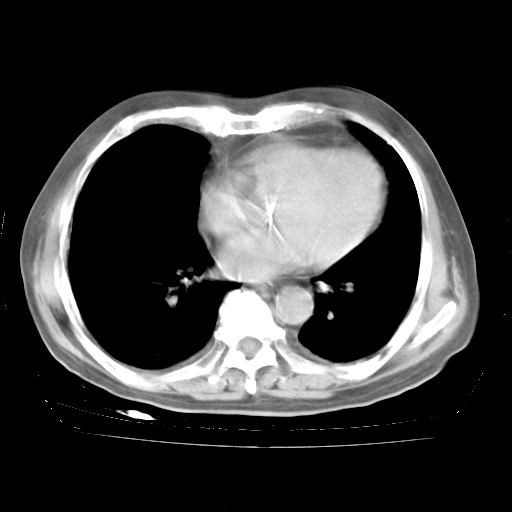

4月28日肺部CT——再次出现类似去年5月9日——透光度降低,“间质性”改变。